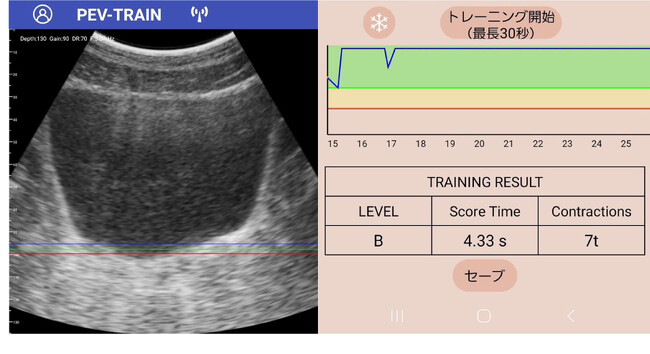

▲専用アプリで見た骨盤底筋の様子と、トレーニング結果を示すデータ

- 「アプリが自動で効果を計測」 「収縮幅」「収縮時間」を自動レコーディングし、トレーニング成果を一目で把握。

- 結果はその場で画面表示、効果をすぐに確認可能